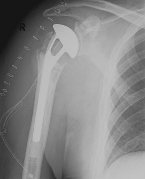

Abbildung2Abbildung1

left: X-ray image of an omarthrosis

right: X-ray of a healthy shoulder joint

X-rays can be used to reliably diagnose the extent of joint wear. In the case of severe osteoarthritis, for example, the joint space and the formation of jagged edges (osteophytes) can be detected. If additional damage to the tendons of the shoulder (rotator cuff) is suspected, ultrasound examination (sonography) or magnetic resonance imaging (MRI) can help clarify the situation.